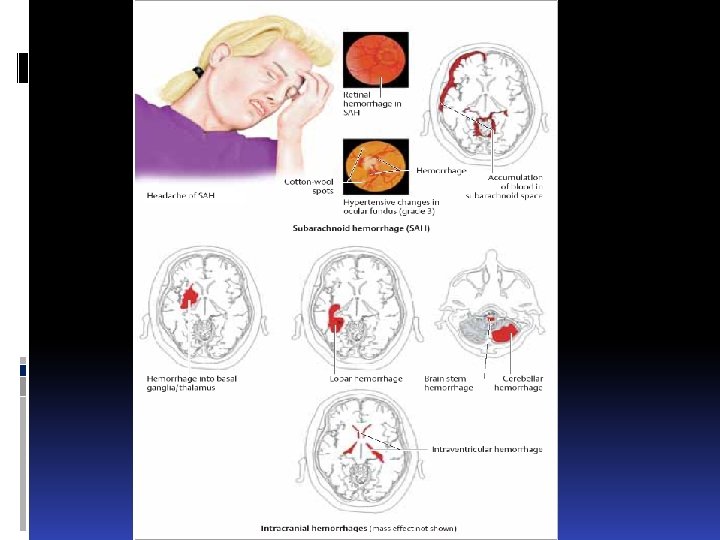

ГЕМОРРАГИЧЕСКИЕ ИНСУЛЬТЫ hemorrhagical s. Паренхиматозные (латеральные и медиаль-ные) субарахноидальные желудочковые паренхиматозно-субарахноидальные паренхиматозно-желудочковые Субдуральные Parenchomatous Subarachnoidal Ventricular Subdural

ГЕМОРРАГИЧЕСКИЕ ИНСУЛЬТЫ hemorrhagical s. Паренхиматозные (латеральные и медиаль-ные) субарахноидальные желудочковые паренхиматозно-субарахноидальные паренхиматозно-желудочковые Субдуральные Parenchomatous Subarachnoidal Ventricular Subdural

Острое нарушение кровоснабжения головного мозга Acute disturbance of brain blood circulation Геморрагический Ишемический

Острое нарушение кровоснабжения головного мозга Acute disturbance of brain blood circulation Геморрагический Ишемический

геморрагические инсульты Субарахноидальное кровоизлияние subarachnoid hemorrhage Разрыв внутричерепной аневризмы Расслоение внутричерепной артерии Геморрагический диатез Тромбоз мозговых вен Травма Hemorrhagic diathesis Trombosis of brain veins Trauma

геморрагические инсульты Субарахноидальное кровоизлияние subarachnoid hemorrhage Разрыв внутричерепной аневризмы Расслоение внутричерепной артерии Геморрагический диатез Тромбоз мозговых вен Травма Hemorrhagic diathesis Trombosis of brain veins Trauma

геморрагические инсульты Желудочковые кровоизлияния Ventricular hemorrhages сознание нарушается вплоть до глубокой комы выраженные нарушения дыхания сердечно-сосудистой деятельности нарушение терморегуляции (резкая гипертермия – свыше 41, 5 – 42 С). Coma Breathing failure Cardiovascular disfunction Termoregulation failure

геморрагические инсульты Желудочковые кровоизлияния Ventricular hemorrhages сознание нарушается вплоть до глубокой комы выраженные нарушения дыхания сердечно-сосудистой деятельности нарушение терморегуляции (резкая гипертермия – свыше 41, 5 – 42 С). Coma Breathing failure Cardiovascular disfunction Termoregulation failure